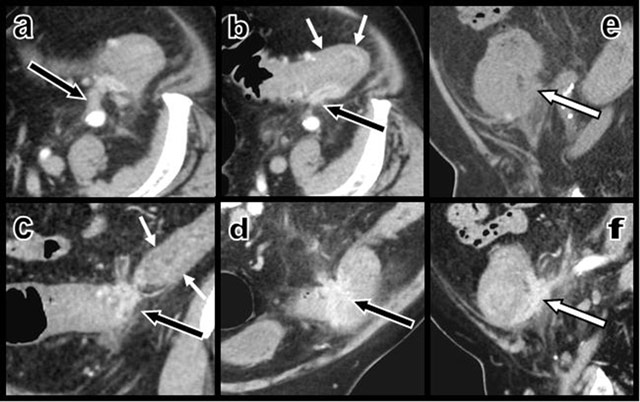

A short contrast-enhancing “scar-like” intra- and extraparietal structure was found infiltrating the posterior colonic wall at the level of the sigmoid and descending colonic junction (Figure 2). This curvilinear retractile “scar-like” tissue had developed multiple adherences with the retroperitoneum and the left iliac fossa and seemed to be stapling the colon on the retroperitoneum.

Figure 2

Contrast-enhanced axial CT views (a and b) and coronal oblique (c and d) multiplanar reconstructions (MPR) show a contrast-enhancing “scar-like” structure (black arrows) infiltrating the thickened colonic wall – due to a hypertrophy of the muscular layers (small white arrows) as confirmed by ultrasound – at the level of the sigmoid and descending colonic junction. This retracting tissue develops multiple adherences with the retroperitoneum. Sagital MPR views before (e) and after (f) intravenous iodine contrast injections illustrate the sharp enhancement of the curvilinear retractile “scar” (white arrow) that infiltrates the colonic wall and staples the colon on the retroperitoneum.